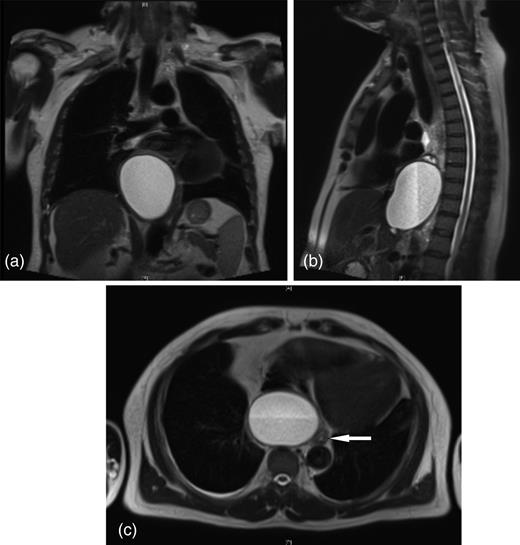

A 52-year-old gentleman, otherwise well, presented with a 3-month history of progressive dysphagia, unable to tolerate solids. An upper gastrointestinal (GI) endoscopy showed extrinsic compression of the lower oesophagus from the posterior aspect, with normal oesophageal mucosa and no gastric abnormality. CT and MRI scanning (Fig. 1) revealed the cause of the compression to be a cystic mass (9.8 × 6.4 × 6.3 cm) in the posterior mediastinum, at the level of the inferior wall of the heart causing compression of the left atrium and displacing the oesophagus to the left (Fig. 1c). The lesion had low attenuation with dependent calcified debris.

Posterior mediastinal cyst causing displacement of the distal oesophagus extending through the diaphragmatic hiatus into the retroperitoneum (a) coronal (b) sagittal and (c) transverse views (arrow denotes oesophagus).